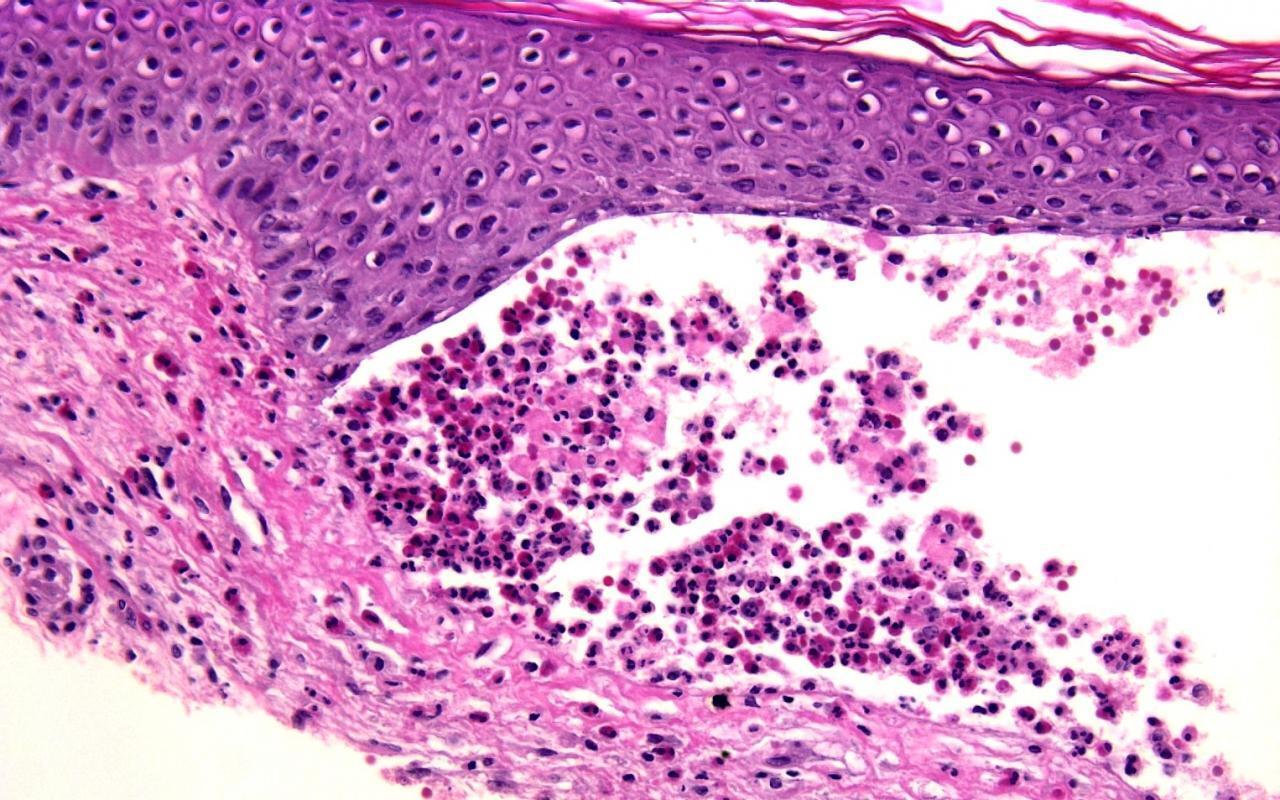

1. A 60-year-old man presents with a poorly demarcated, symmetric, very painful patches of erythema and retiform purpura favoring the buttocks. Bullae and a dusky gray discoloration developed and ulcerations appeared with a black, leathery eschar. Upon palpation there is a surrounding subcutaneous induration that extends beyond the margins of the visibly active lesions. You perform a skin biopsy (see image). Which of the following is the most likely diagnosis?

Correct choice: A. Calciphylaxis

Explanation: calciphylaxis is characterized by intimal fibrosis and medial vascular calcification (that can become transmural) as well as transdifferentiation of vascular smooth muscle cells into osteoblast-like cells; these changes plus thrombosis lead to ischemic necrosis of the skin and soft tissues. Early lesions usually present as poorly demarcated, often symmetric, very painful patches of erythema or retiform purpura. They favor areas with abundant adipose tissue or sites of trauma. Bullae or a dusky gray color may then develop, signifying imminent tissue necrosis and the appearance of ulcerations with black, leathery eschars. Often there is surrounding subcutaneous induration that extends beyond the margins of the visibly active lesions and this can be helpful in distinguishing calciphylaxis from other forms of retiform purpura.